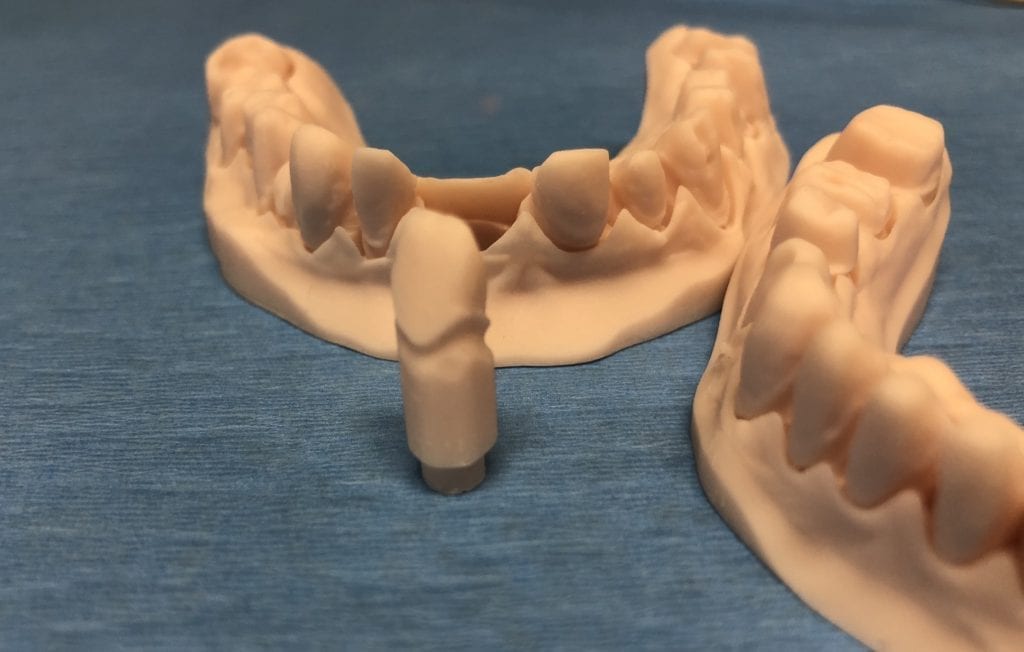

The case was designed by CADENT BESSA, and the models were printed by Burbank Dental Lab with Carbon Printers. There restorations were milled and cut back and layered by Burbank Dental Lab

IMAGES OF PRINTED MODELS